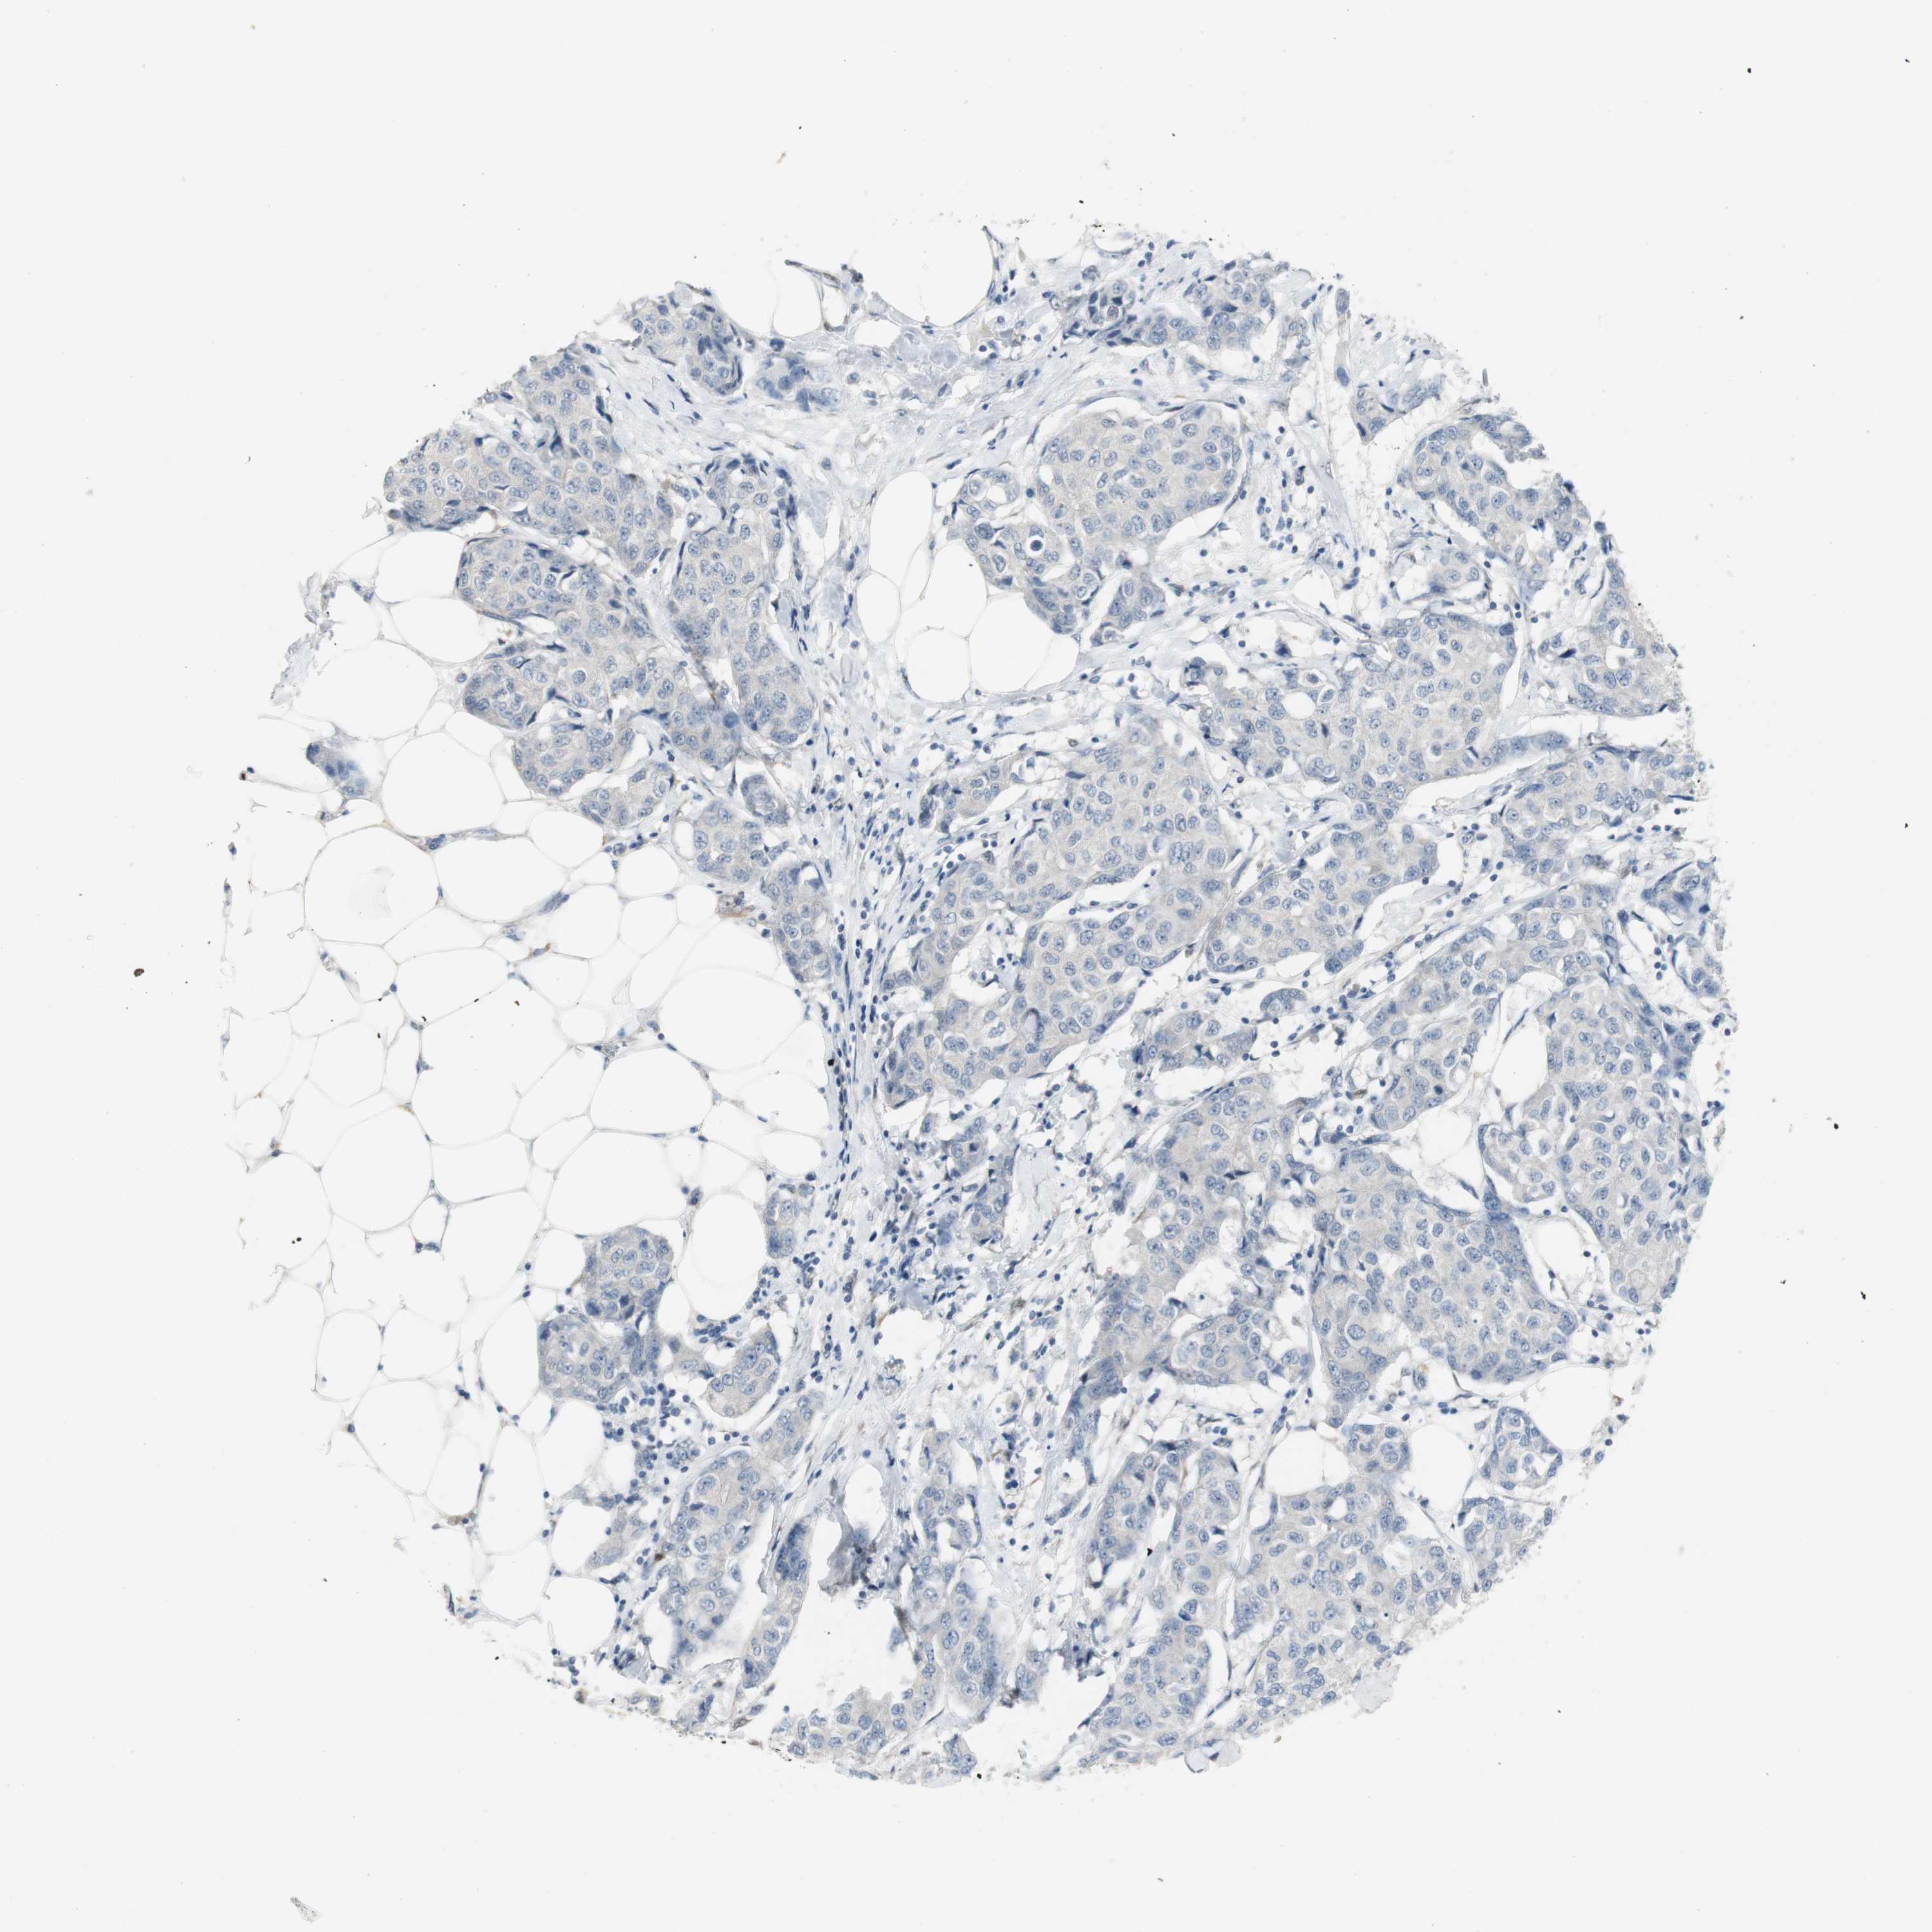

CANCER BREAST CANCER Show tissue menu

BRCA TCGA BRCA VALIDATION PROTEIN EXPRESSION

Breast cancer

Human cancer